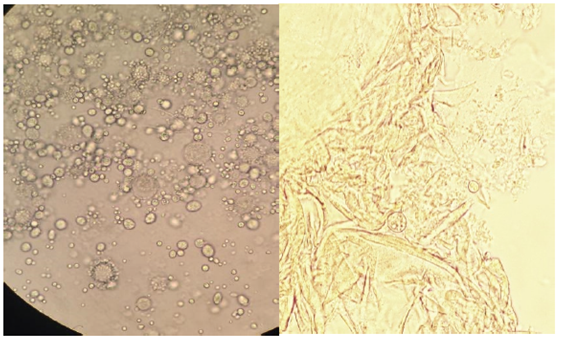

El estudio micológico de la lesión orofaríngea mostró en el examen directo (fresco y frotis coloreados) la presencia de levaduras redondas, grandes, multibrotantes, (con aspecto de rueda de timón), de pared fina, con morfología característica del género Paracoccidioides. En los cultivos en medio Sabouraud Dextrosa, Sabouraud Cloramfenicol y Sabouraud con Cloramfenicol y Cicloheximida, desarrolló un hongo dimorfo que a 28°C se presentaba en su fase filamentosa y a 37°C en su fase levaduriforme (Figura 4).

Figura 4: Estudio micológico directo de la lesión orofaríngea. Foto obtenida por la Dra. Anaydé Lena

En el directo se observó microscópicamente la levadura, con múltiples brotes constituyendo la imagen clásica de esta micosis en rueda de timón.

En los cultivos se observó el crecimiento tanto de filamentos a 28°C como de levaduras a 37°C. Al principio se observó a 28°C la presencia simultánea de filamentos y levaduras, que se interpretan como formas de transición.